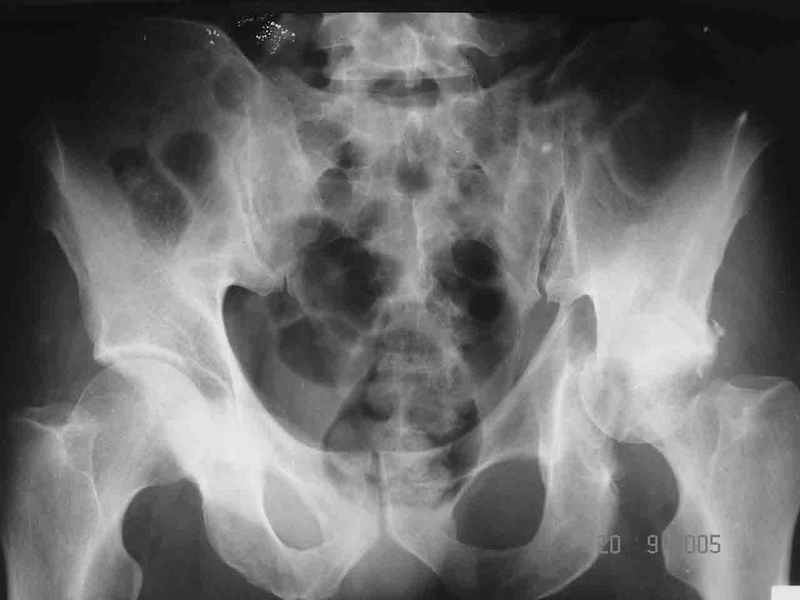

Контрольный снимок перед разрешением нагрузки прямой 13/10/03

|

Перед разрешением нагрузки боковой 13/10/03

Два месяца нагрузки без костылей 19/12/03

Еще месяц 20/02/04

Больной 18 мая 2003 года в автоаварии получил перелом левой вертлужной впадины, вывих бедра. Госпитализирован в один из стационаров области.Вывих вправлен. В последствии бедро вывихивалось еще дважды. На консультацию был представлен снимок от 19.05.03г., больной переведен к нам 3.06.03г. Снимок при поступлении - перелом впадины, задне-верхний вывих бедра. 05.06.2003 г. выполнено открытое вправление вывиха левого бедра и остеосинтез стенки вертлужной впадины двумя винтами. Послеоперационный период без осложнений. Объем движений в левом тазобедренном суставе восстановился полностью. Выписан на амбулаторное лечение в удовлетворительном состоянии с рекомендациями 3 месяца ходить на костылях без нагрузки на оперированную конечность. На контрольных рентгенограммах левого тазобедренного сустава 13.10.2003 г. - признаки консолидации перелома; плотность, форма головки и состояние суставных поверхностей удовлетворительные. Разрешена дозированная осевая нагрузка, на конечность с использованием дополнительной опоры. 19.12.2003 г. больной обратился с жалобами на боли в левом тазобедренном суставе. На рентгенограммах левого тазобедренного сустава 19.12.2003 г., 20.02.04г. - асептичекий некроз головки бедра. 5.04.04г. - эндопротез. Сейчас ходит без трости, не хромает. Особенность эндопротезирования - при удалении винтов прослежена линия перелома заднего края впадины и предложено установить чашку несколько меньшего диаметра, чтобы она была покрыта несломанной частью.